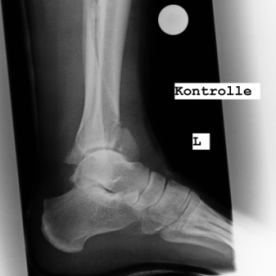

1) Bandverletzungen des oberen Sprunggelenkes

Bandverletzungen des oberen Sprunggelenkes sind sehr häufig und werden durch ein Wegknicken im oberen Sprunggelenk nach außen oder innen hervorgerufen. Es handelt sich jeweils um eine Verletzung des inneren oder äußeren Kapselbandapparat. Die verschiedenen Außenbänder verstärken den Kapselbandapparat auf der Außenseite und das Innenband verstärkt den inneren Kapselbandapparat über mehrere Zügel in verschieden Richtungen. Es können Bänderdehnungen von Teilrissen und kompletten Rissen unterschieden werden. Bei relevanten Verletzungen kommt es zu einer vorübergehenden Instabilität des oberen Sprunggelenkes außen- oder innenseitig.Die Bandverletzung im Bereich des oberen Sprunggelenkes ist seit vielen Jahren eine Domäne der konservativen Behandlung, es sollte für 4-6 Wochen eine Sprunggelenksorthese zum Schutz des äußeren, bzw. inneren Kapselbandapparates getragen werden, danach ist mit einer Ausheilung der Bandverletzung zu einem ganz hohem Prozentsatz zu rechnen. Nur bei ausbleibender Stabilität und immer wieder kehrenden Instabilitätsattacken wäre ein operatives Vorgehen in Form einer Bandplastik notwendig.

Röntgenbilder